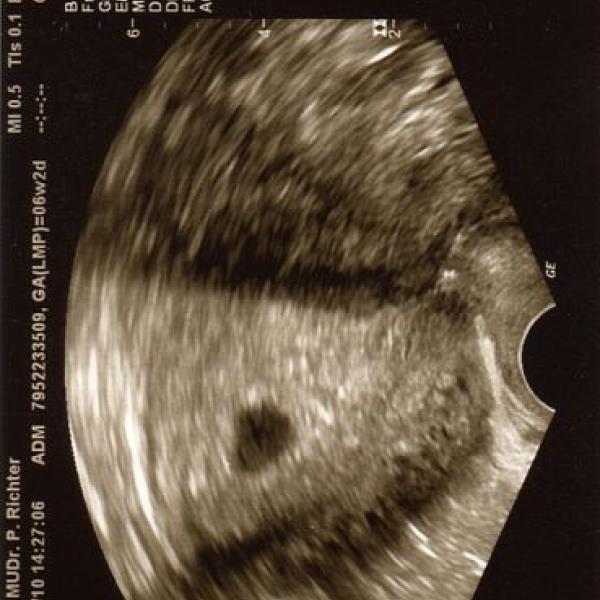

TAK SE JDU TAKÉ UKÁZAT S FOTEČKOU JE TO TO ZATÍM PIDI MINI ALE JE TAM :\x: :\x: :\x: :\x: :\x: :\x: :\x: :\x: :\x:

PODLE MENSTR. BYCH MĚLA BÝT 6+4tt ALE PODRE UTZ ASI JEN 5+4tt :$$: :$$: :$$:

OVU SE DOSTAVILA PRAVDĚPODOBNĚ POZDĚJI :dance: :dance: :dance: :dance: TAK SE MĚJTE KRÁSNĚ PÁÁÁÁÁÁÁÁÁÁÁÁÁÁÁÁÁÁÁÁÁÁÁÁÁ :a: :a: :a: :a: :a: